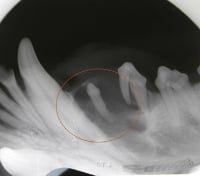

Periodontal disease

Source: Dr. Brett Beckman